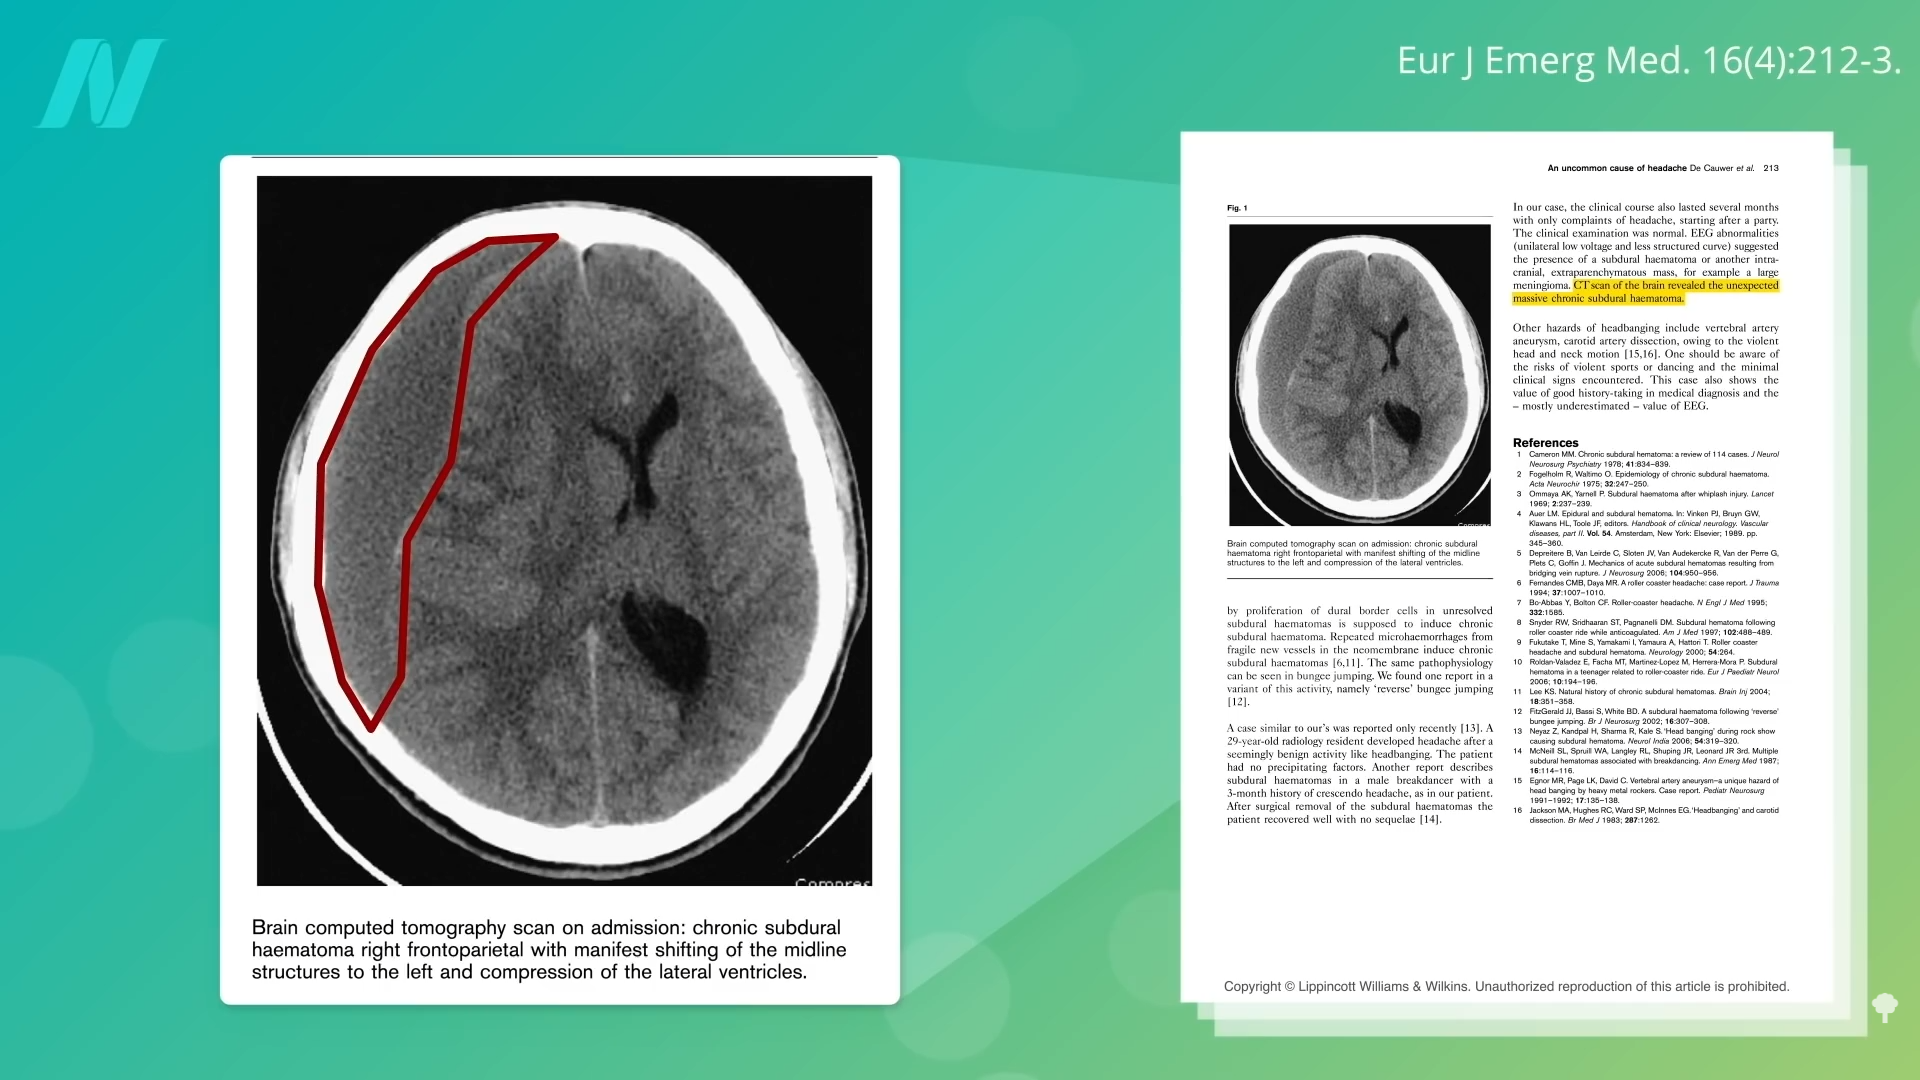

The researchers conclude that their “case serves as evidence in support of Motörhead’s reputation as one of the most hardcore rock’n’roll acts on earth,” but I think the real takeaway is that a potentially dangerous complication like subdural hematoma can result from “a seemingly benign activity like head banging.” And some of the brain bleeds can be massive. One man complained of a “headache after headbanging at a party.” Why? As you can see in his CT scan below and at 5:35, circled in red is all blood, squishing over his brain. Amazingly, he survived; another man didn’t, headbanging and losing his life to a fatal subdural hemorrhage.